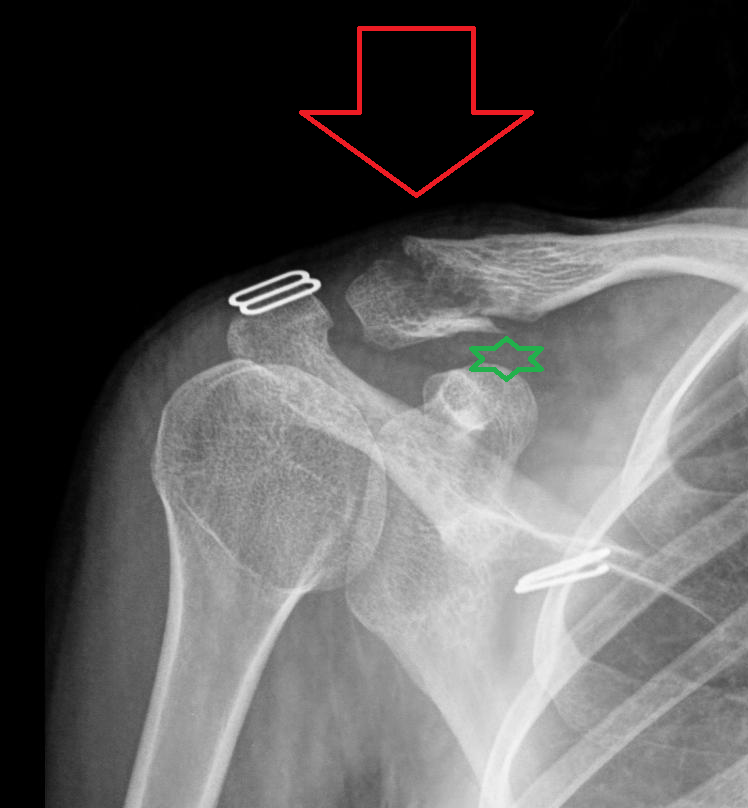

From www.researchgate.net

Tenyearold boy with a right clavicle fracture treated with an ESIN. a... Download Scientific Clavicle Fracture Future Problems Most collarbone fractures heal on their own with. Acute fractures of the proximal third of the clavicle often stem from high energy trauma and are associated with severe internal. The clavicle (collarbone) is one of the most fractured bones in the body. Midshaft clavicle fractures are common traumatic injuries caused by a direct impact to the shoulder girdle and is. Clavicle Fracture Future Problems.

From ar.inspiredpencil.com

Proximal Clavicle Fracture Clavicle Fracture Future Problems Our study revealed that patients with clavicle fractures treated with plate fixation had statistically significant good functional. Most collarbone fractures heal on their own with. Midshaft clavicle fractures are common traumatic injuries caused by a direct impact to the shoulder girdle and is most commonly seen in young, active adults. Despite conflicting evidence, most studies indicate that superior clinical results.. Clavicle Fracture Future Problems.